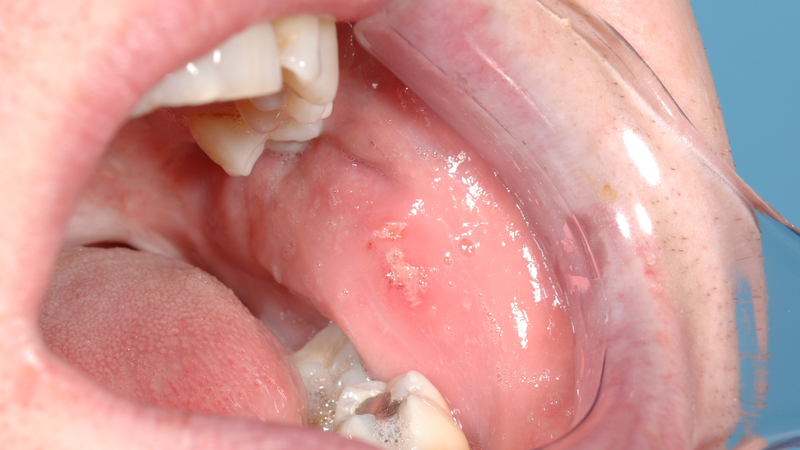

Niêm mạc miệng là một lớp màng mỏng và nhạy cảm, dễ bị tổn thương. Một số dấu hiệu nhận biết niêm mạc bất thường bao gồm:

Nhận biết được các dấu hiệu này sẽ giúp bạn duy trì sức khỏe răng miệng tốt hơn và nhanh chóng tìm kiếm sự hỗ trợ từ chuyên gia khi cần.